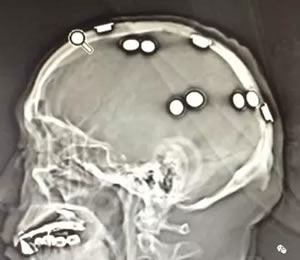

今日,人民解放军第101医院功能神经外科与清华大学玉泉医院癫痫中心通过远程会诊的方式,进行了2例难治性癫痫的病例讨论。讨论过程中,通过分析患者的临床症状学、长程脑电图、影像学及影像后处理,明确了患者的下一步治疗方案。患者无需四处奔波,即可得到满意的治疗效果。

在周文静主任的带领下,清华大学玉泉医院癫痫中心现已成为全国知名的癫痫治疗中心。率先在国内开展颅内深部电极置入(SEEG)及热凝毁损技术,并依托于清华大学科研团队,承担一系列国家重大的科研课题。